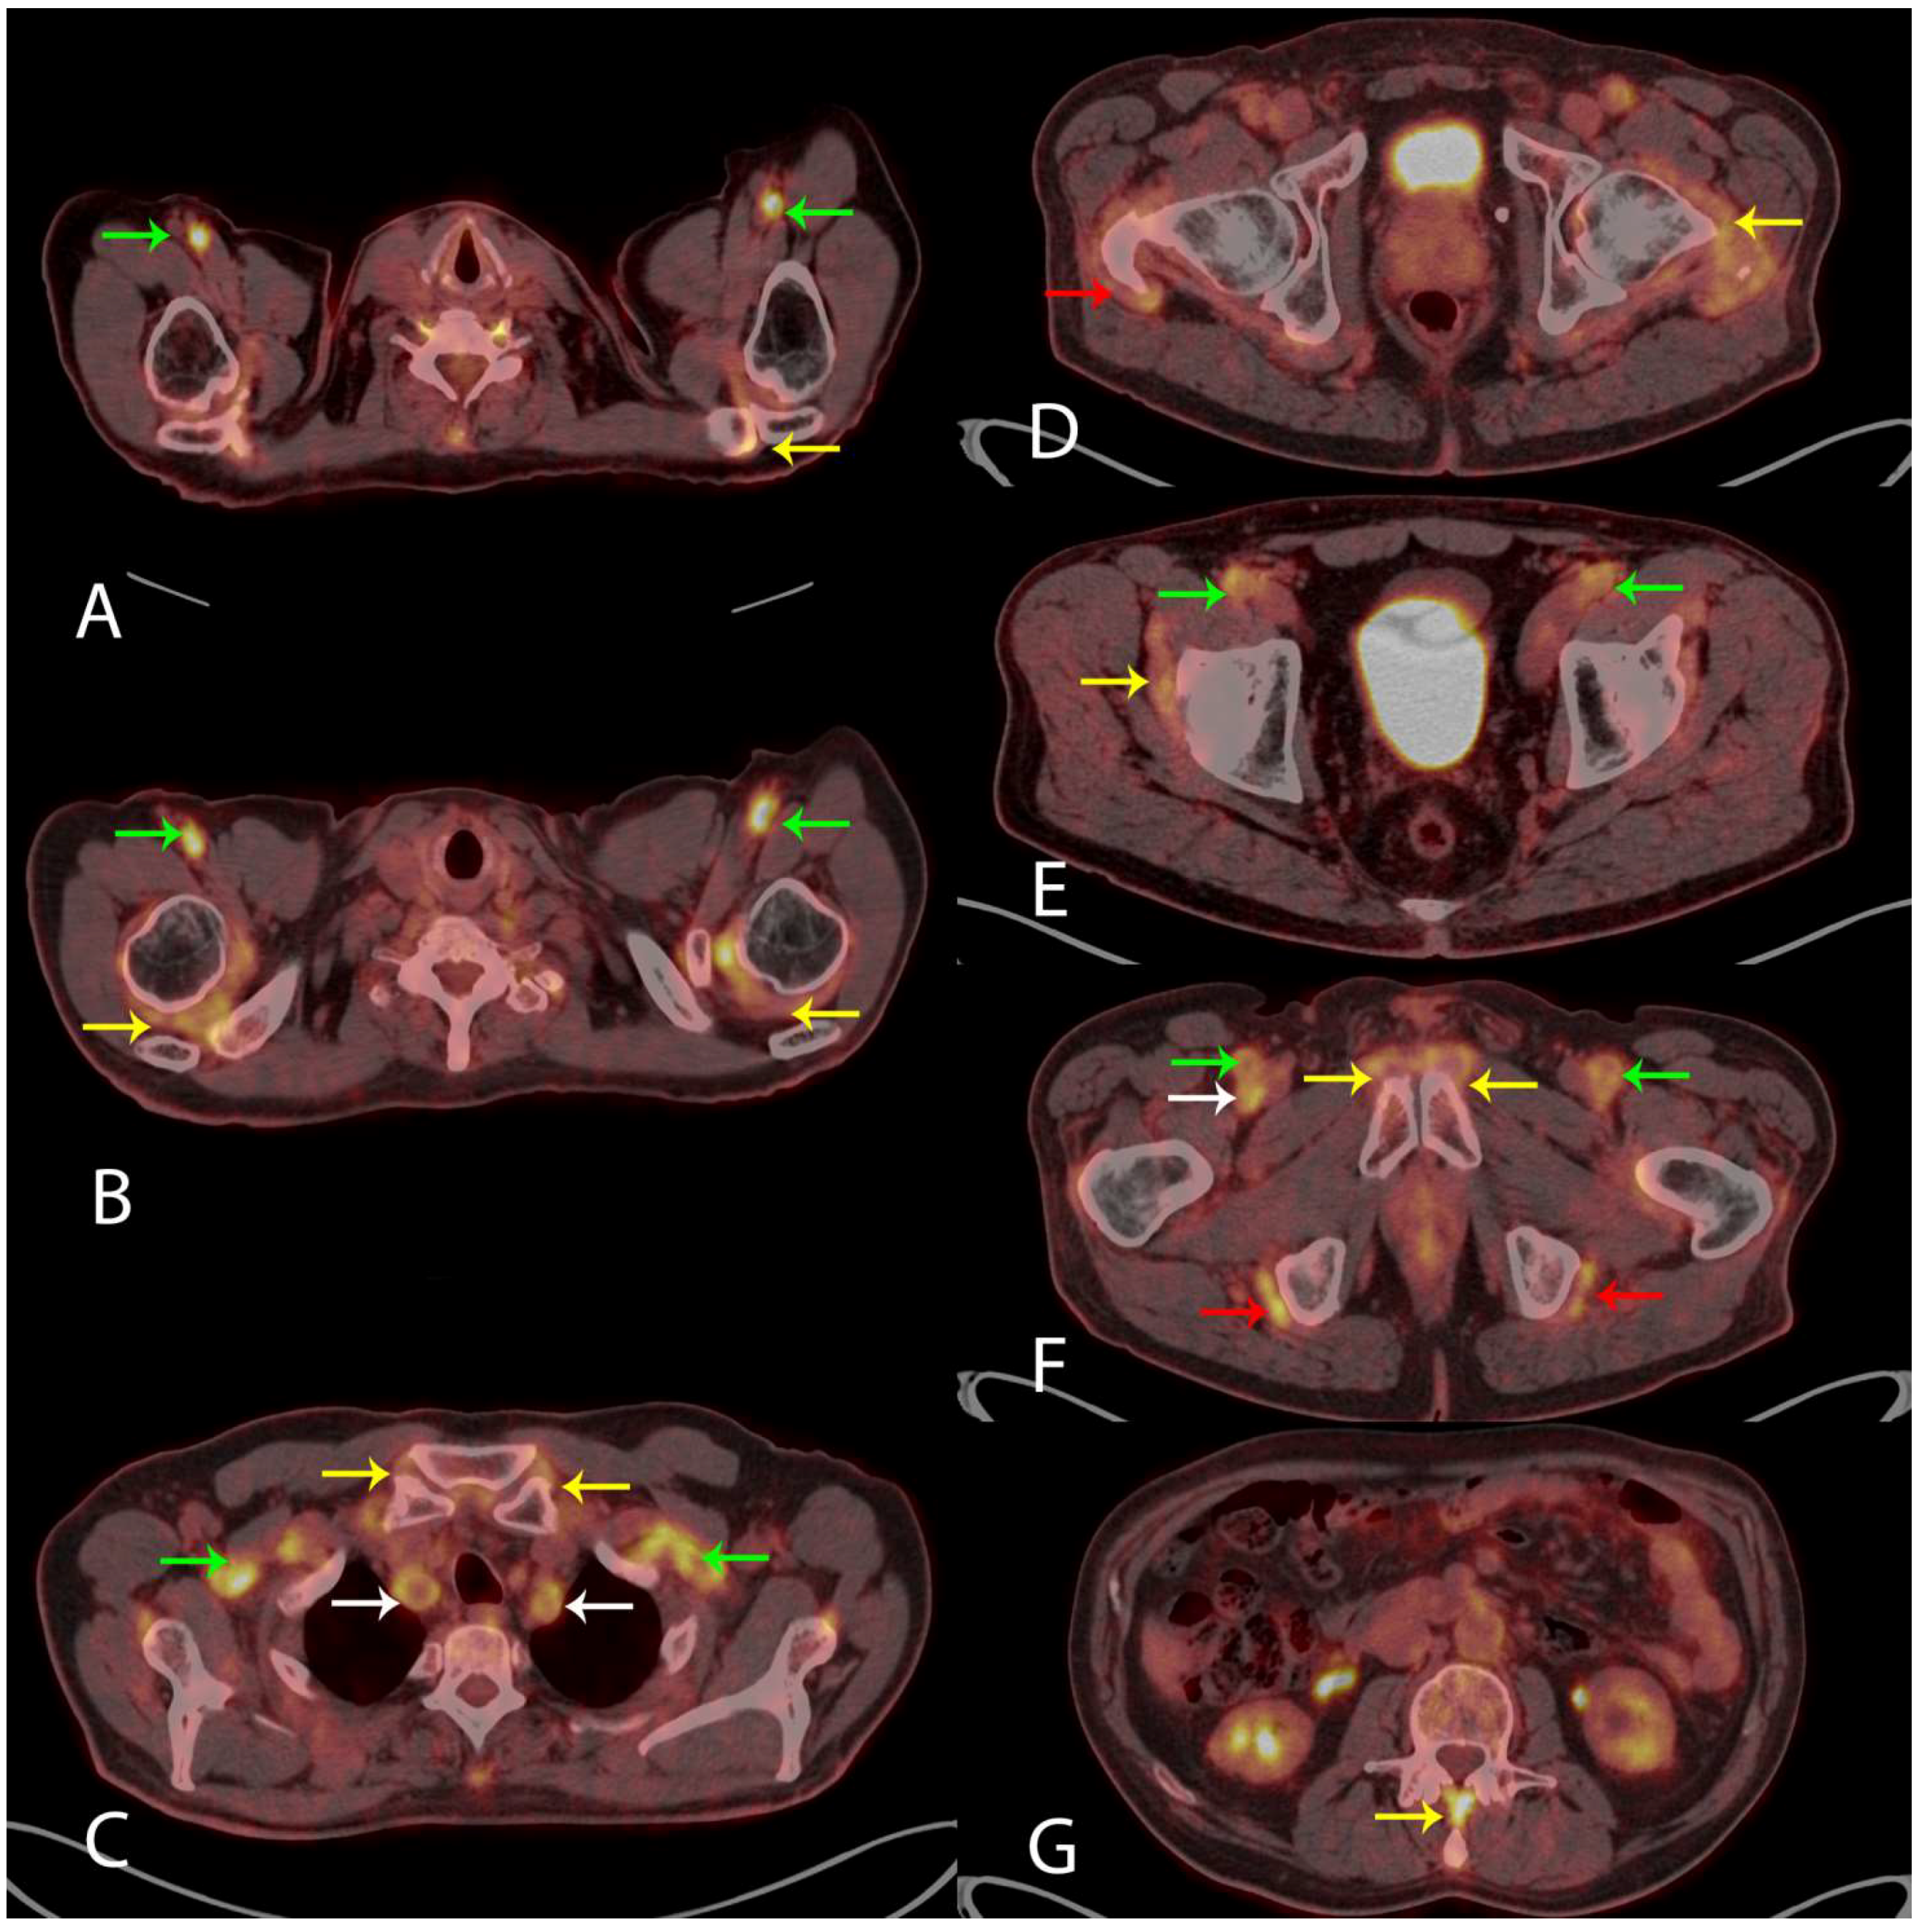

Visually measuring the 18F-FDG uptake in nine anatomical sites when evaluating the PET/CT scan for the diagnosis of PMR has been suggested [5,6]. These sites include: acromioclavicular joints (A) axial fused PET/CT (yellow arrow, left side shown), the high 18F-FDG uptake in the axillary arteries indicates LVV (green arrows); shoulder joints (B) axial fused PET/CT (yellow arrows), LVV in axillary arteries (green arrows); sternoclavicular joints (C) axial fused PET/CT (yellow arrows), LVV in subclavian arteries (green arrows) and common carotid arteries (white arrows); hip joints (D) axial fused PET/CT (yellow arrow, left side shown) and greater trochanter (D) axial fused PET/CT (red arrow, right side shown); the two iliopectinal bursae (E) axial fused PET/CT (yellow arrow, right side shown), LVV in common femoral arteries (green arrows); two symphysis pubis enthesis (F) axial fused PET/CT (yellow arrows) and two ischial tuberosities (F) axial fused PET/CT (red arrows), LVV in superficial femoral arteries (green arrows) and right profound femoral artery (white arrow); and interspinous ligaments (G) axial fused PET/CT (yellow arrow), respectively. The specificity of 18F-FDG PET/CT in the diagnosis of PMR is 95% given that the 18F-FDG uptake is above the uptake in the liver in ≥6 anatomical sites [5]. In our case, the 18F-FDG uptake met this criterion in all nine anatomical sites (not quantitatively shown). No malignancy was visualized. Based on the clinical information and the results of the 18F-FDG PET/CT, the patient was treated with 60 mg of Prednisolone resulting in the normalization of blood tests and rapid remission of symptoms. Our case shows that 18F-FDG PET/CT is a strong supportive imaging tool in the diagnosis of PMR and LVV. 18F-FDG PET/CT can be used where malignancy is a differential diagnosis, as proposed in the newest European League Against Rheumatism (EULAR) recommendations [7].